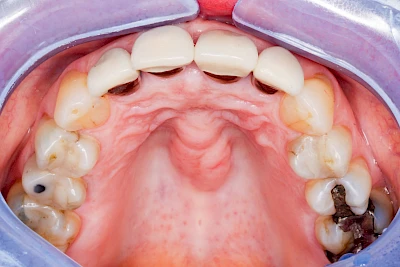

Überbeine im Bereich der Kiefer sind gar nicht so selten. Häufiger im Bereich der Seitenzähne unterhalb des Zahnfleisches, aber auch in der Mitte vom Gaumen. Überbeine haben in dem Sinne keinen Krankheitswert, müssen also nicht operativ entfernt werden, wenn diese nicht stören. Überbeine können ein Anzeichen für Knirschen und Pressen sein.